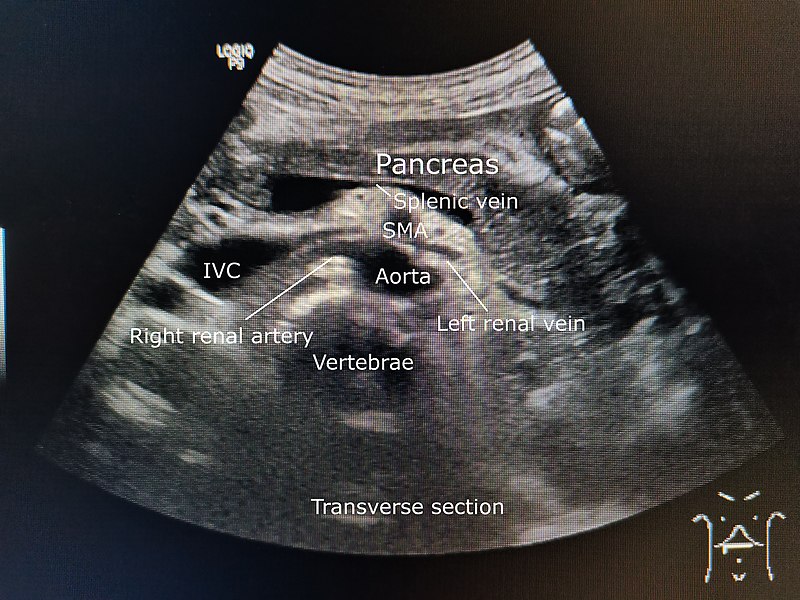

Exocrine Pancreas

The exocrine pancreas is responsible for secretion of ions, water, and digestive enzymes into the duodenum of the gastrointestinal tract.

Endocrine Pancreas

The endocrine pancreas consists of groups of cells known as islets of Langerhans.